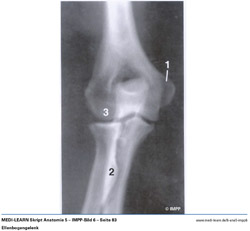

• Ellenbogengelenk